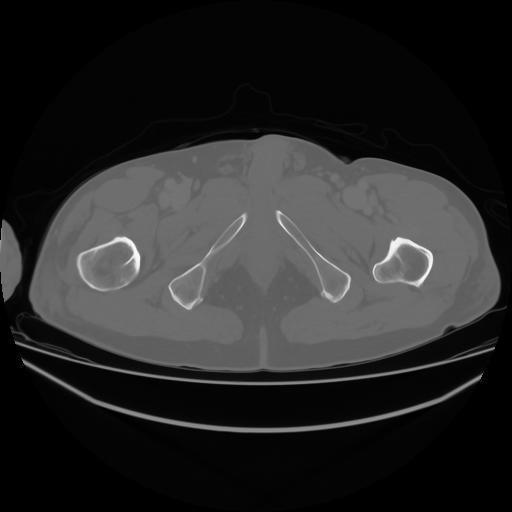

4 CUERPO,CE,Axial,3.0,CUERPO,,